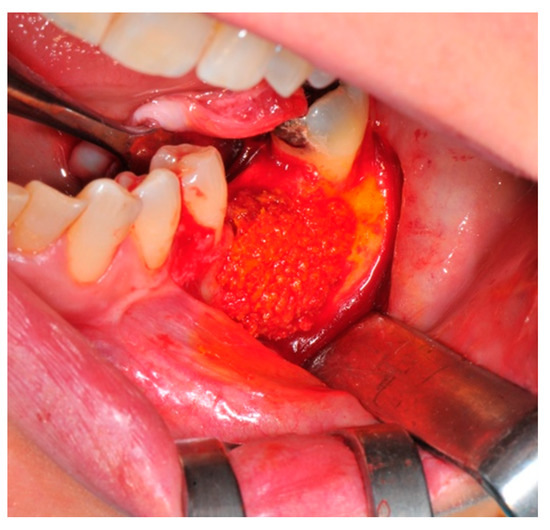

- Particulate bone: At this stage, a 50:50 autologous/heterologous bone mix is grafted both in the atrophic site and within the titanium mesh (Figure 7).